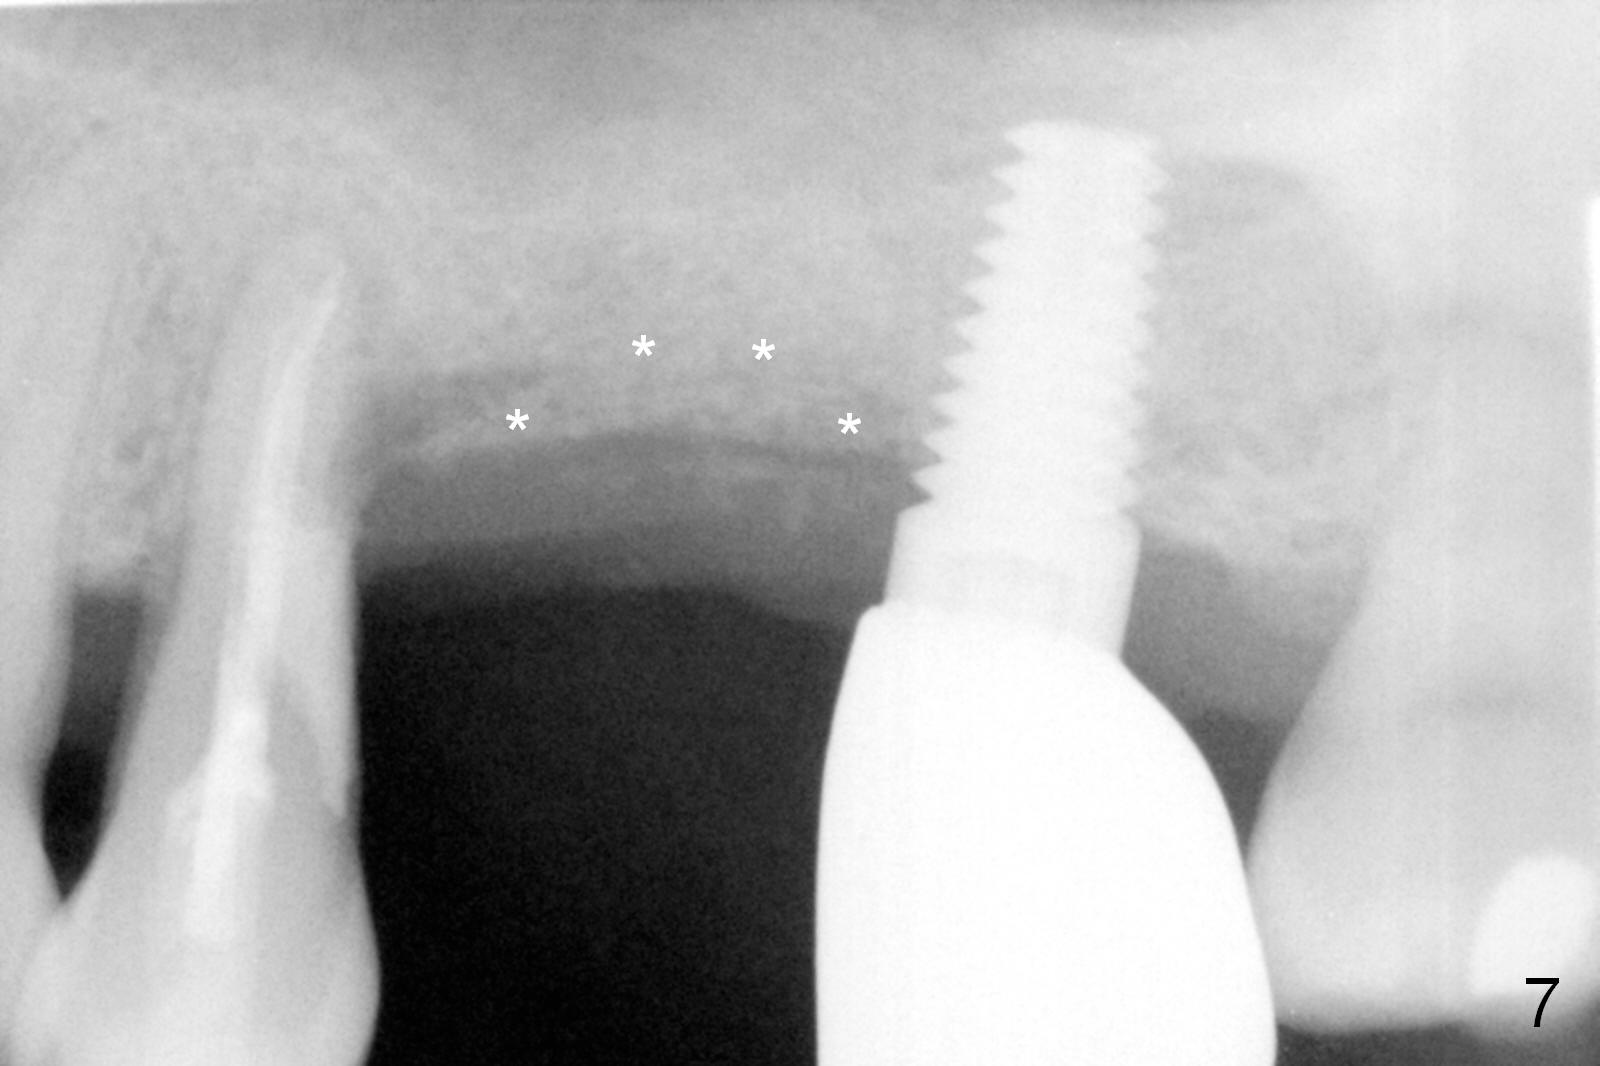

The implant site is healing a few days after loss (Fig.4 *) with a bony defect (Fig.5 ^). It appears that the implant at #14 was placed buccally. An incision is made palatally because of the presence of more keratinized gingiva (Fig.6). The buccal bone height is limited. The soft tissue in the bony defect is lifted into the sinus before bone graft (Fig.7 *).